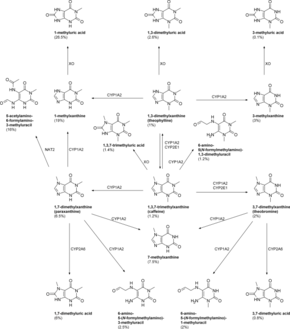

Caffeine is metabolized in the liver by the cytochrome P450 oxidase enzyme system, in particular, by the CYP1A2 isozyme, into three dimethylxanthines,[188] each of which has its own effects on the body:

- Paraxanthine (84%): Increases lipolysis, leading to elevated glycerol and free fatty acid levels in blood plasma.

- Theobromine (12%): Dilates blood vessels and increases urine volume. Theobromine is also the principal alkaloid in the cocoa bean (chocolate).

- Theophylline (4%): Relaxes smooth muscles of the bronchi, and is used to treat asthma. The therapeutic dose of theophylline, however, is many times greater than the levels attained from caffeine metabolism.[47]

1,3,7-Trimethyluric acid is a minor caffeine metabolite.[9] 7-Methylxanthine is also a metabolite of caffeine.[189][190] Each of the above metabolites is further metabolized and then excreted in the urine. Caffeine can accumulate in individuals with severe liver disease, increasing its half-life.[191]